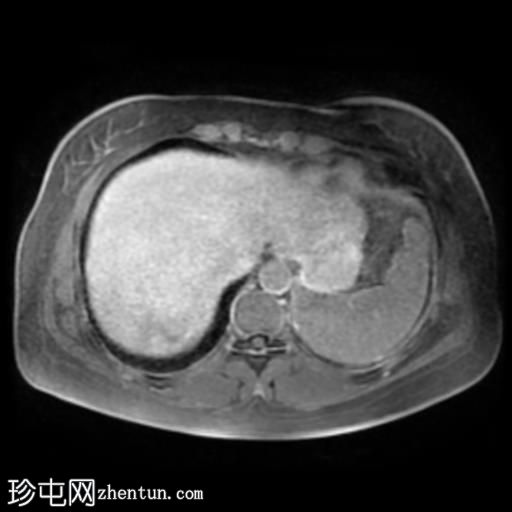

轴位T1加权像

GE IPOP序列

肝脏第7段可见一边界清晰的分叶状肿块。T1加权像呈低信号,T2/T2脂肪抑制序列呈高信号,动脉期呈不连续结节状周边强化,门静脉期呈向心性强化,延迟期完全强化。DWI序列呈高信号,ADC值呈混合信号。